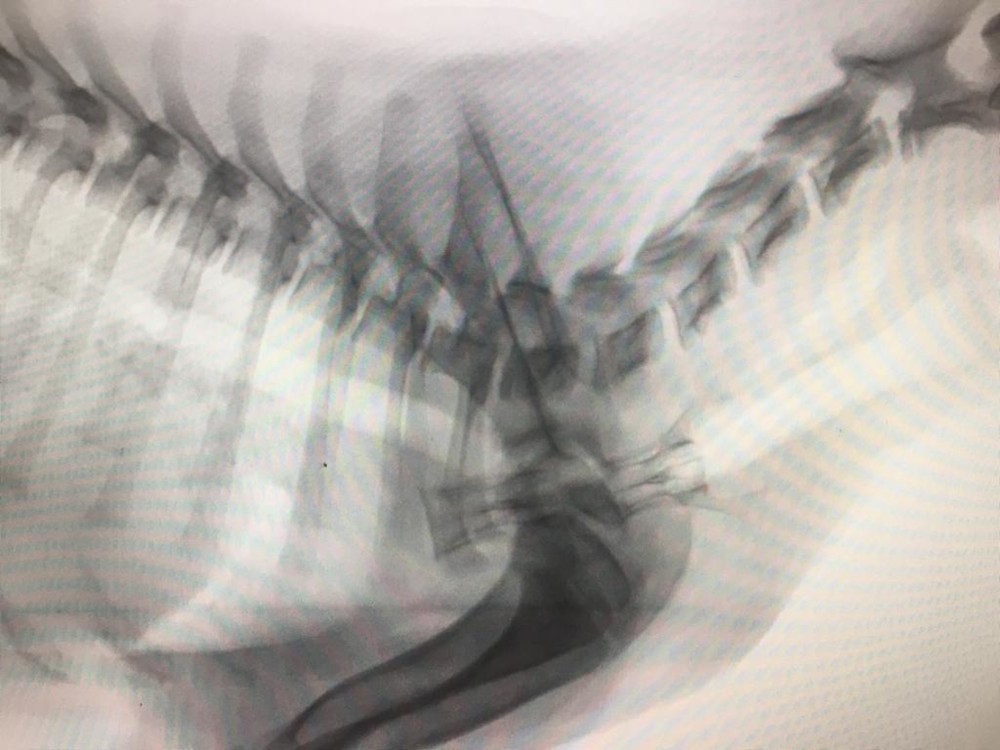

Röntgenfelvétel a nyelőcsőben elakadt csigolyacsontokról

Szomorú esetet osztott meg velünk dr. Pálosi Csaba, a Noé Bárkája kisállatklinika vezetője. Egy három hónapos kölyökkutya nyelőcsövében csigolyacsontok akadtak el. Múlt hét szombatján történt az eset, a gazdája csak hétfőn kereste fel az állatorvosi rendelőt, és kijelentette, hogy nem vállalja sem a beavatkozás, sem az altatás költségeit. Ennek ellenére megpróbálták megmenteni az állat életét, de az eltelt idő alatt az elakadt csont átfúrta a nyelőcsövét, és minden igyekezet ellenére nem sikerült megmenteni az életét. Az eset kapcsán újra terítékre került a felelősségteljes állattartás, az állatok egészségügyi ellátásának szükségszerűsége, az életmentő sürgősségi beavatkozások és nem utolsósorban a csonttal való etetés módja, előnyei és hátrányai.